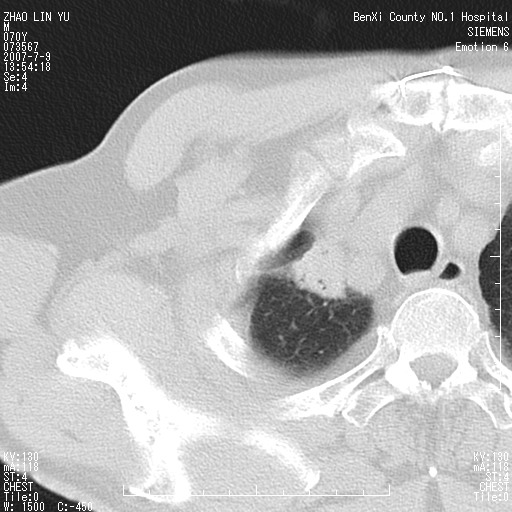

以下是引用王靖旗在2007-7-10 17:12:00的发言:[br] 男、70、咳嗽两个月,半年前换瓣手术,胸片未见异常,于昨天行x片发现右肺上野大片影,行ct扫描,这里是减薄图像,余肺正常。明天晚上会有增强扫描片,到时我会上传。[br][br] 冠状位请大家细看,应该是有意义的,[br][br] 请大家先看平扫发表意见。[br][br]

以下是引用zhangzhongshou在2007-7-10 21:43:00的发言:[br]右肺上叶周围型肺癌,以孤立型细支气管肺泡癌可能性大。